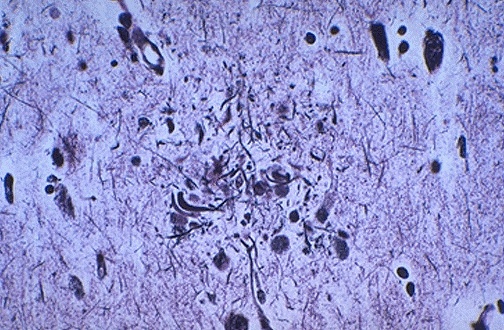

| Here is another Alzheimer neuritic plaque seen with a silver stain that highlights the dystrophic neurites. The major biochemical defect in Alzheimer disease (AD) is a loss of acetylcholine in the cerebral cortex. Cholinesterase inhibitors, which increase the availability of acetylcholine in central synapses, include the drugs tacrine, donepezil, metrifonate, rivastigmine and galantamine, have been employed in the treatment of AD. In addition to an effect on improved cognition and slowing of cognitive decline, they have a positive effect on mood and behavior. The length of the effect is uncertain. The majority of patients with Alzheimer disease have at least one copy of apolipoprotein E4, and these patients seem to have a greater impairment of presynaptic cholinergic function than patients without the apolipoprotein E4 allele, and this might be expected to reduce their response to treatment. |